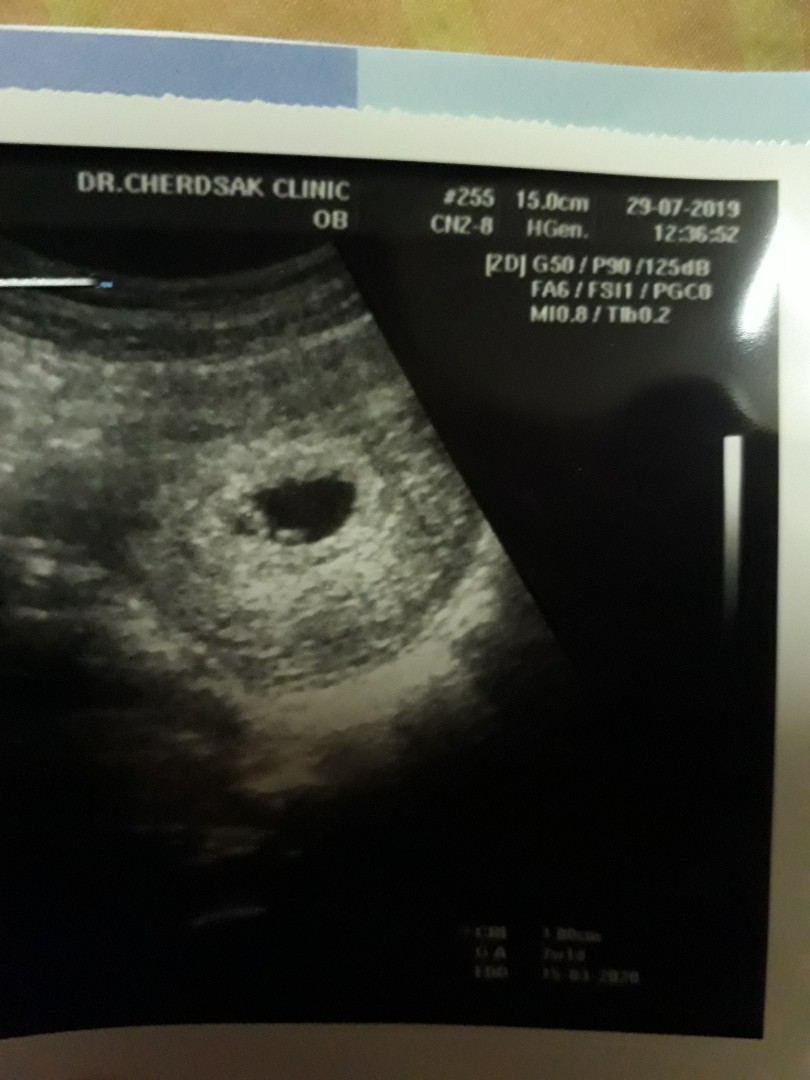

ภาพแรกของลูก❤️

Post reply image